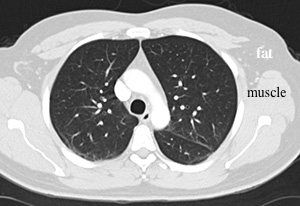

SOFT TISSUE window-does not show lungs very well, does not show marrow cavities in bones (but bones are still visible, just no details), but very good for showing muscles and organs, particularly when outlined by fat, because they are very different in darkness (fat is much darker than muscle)